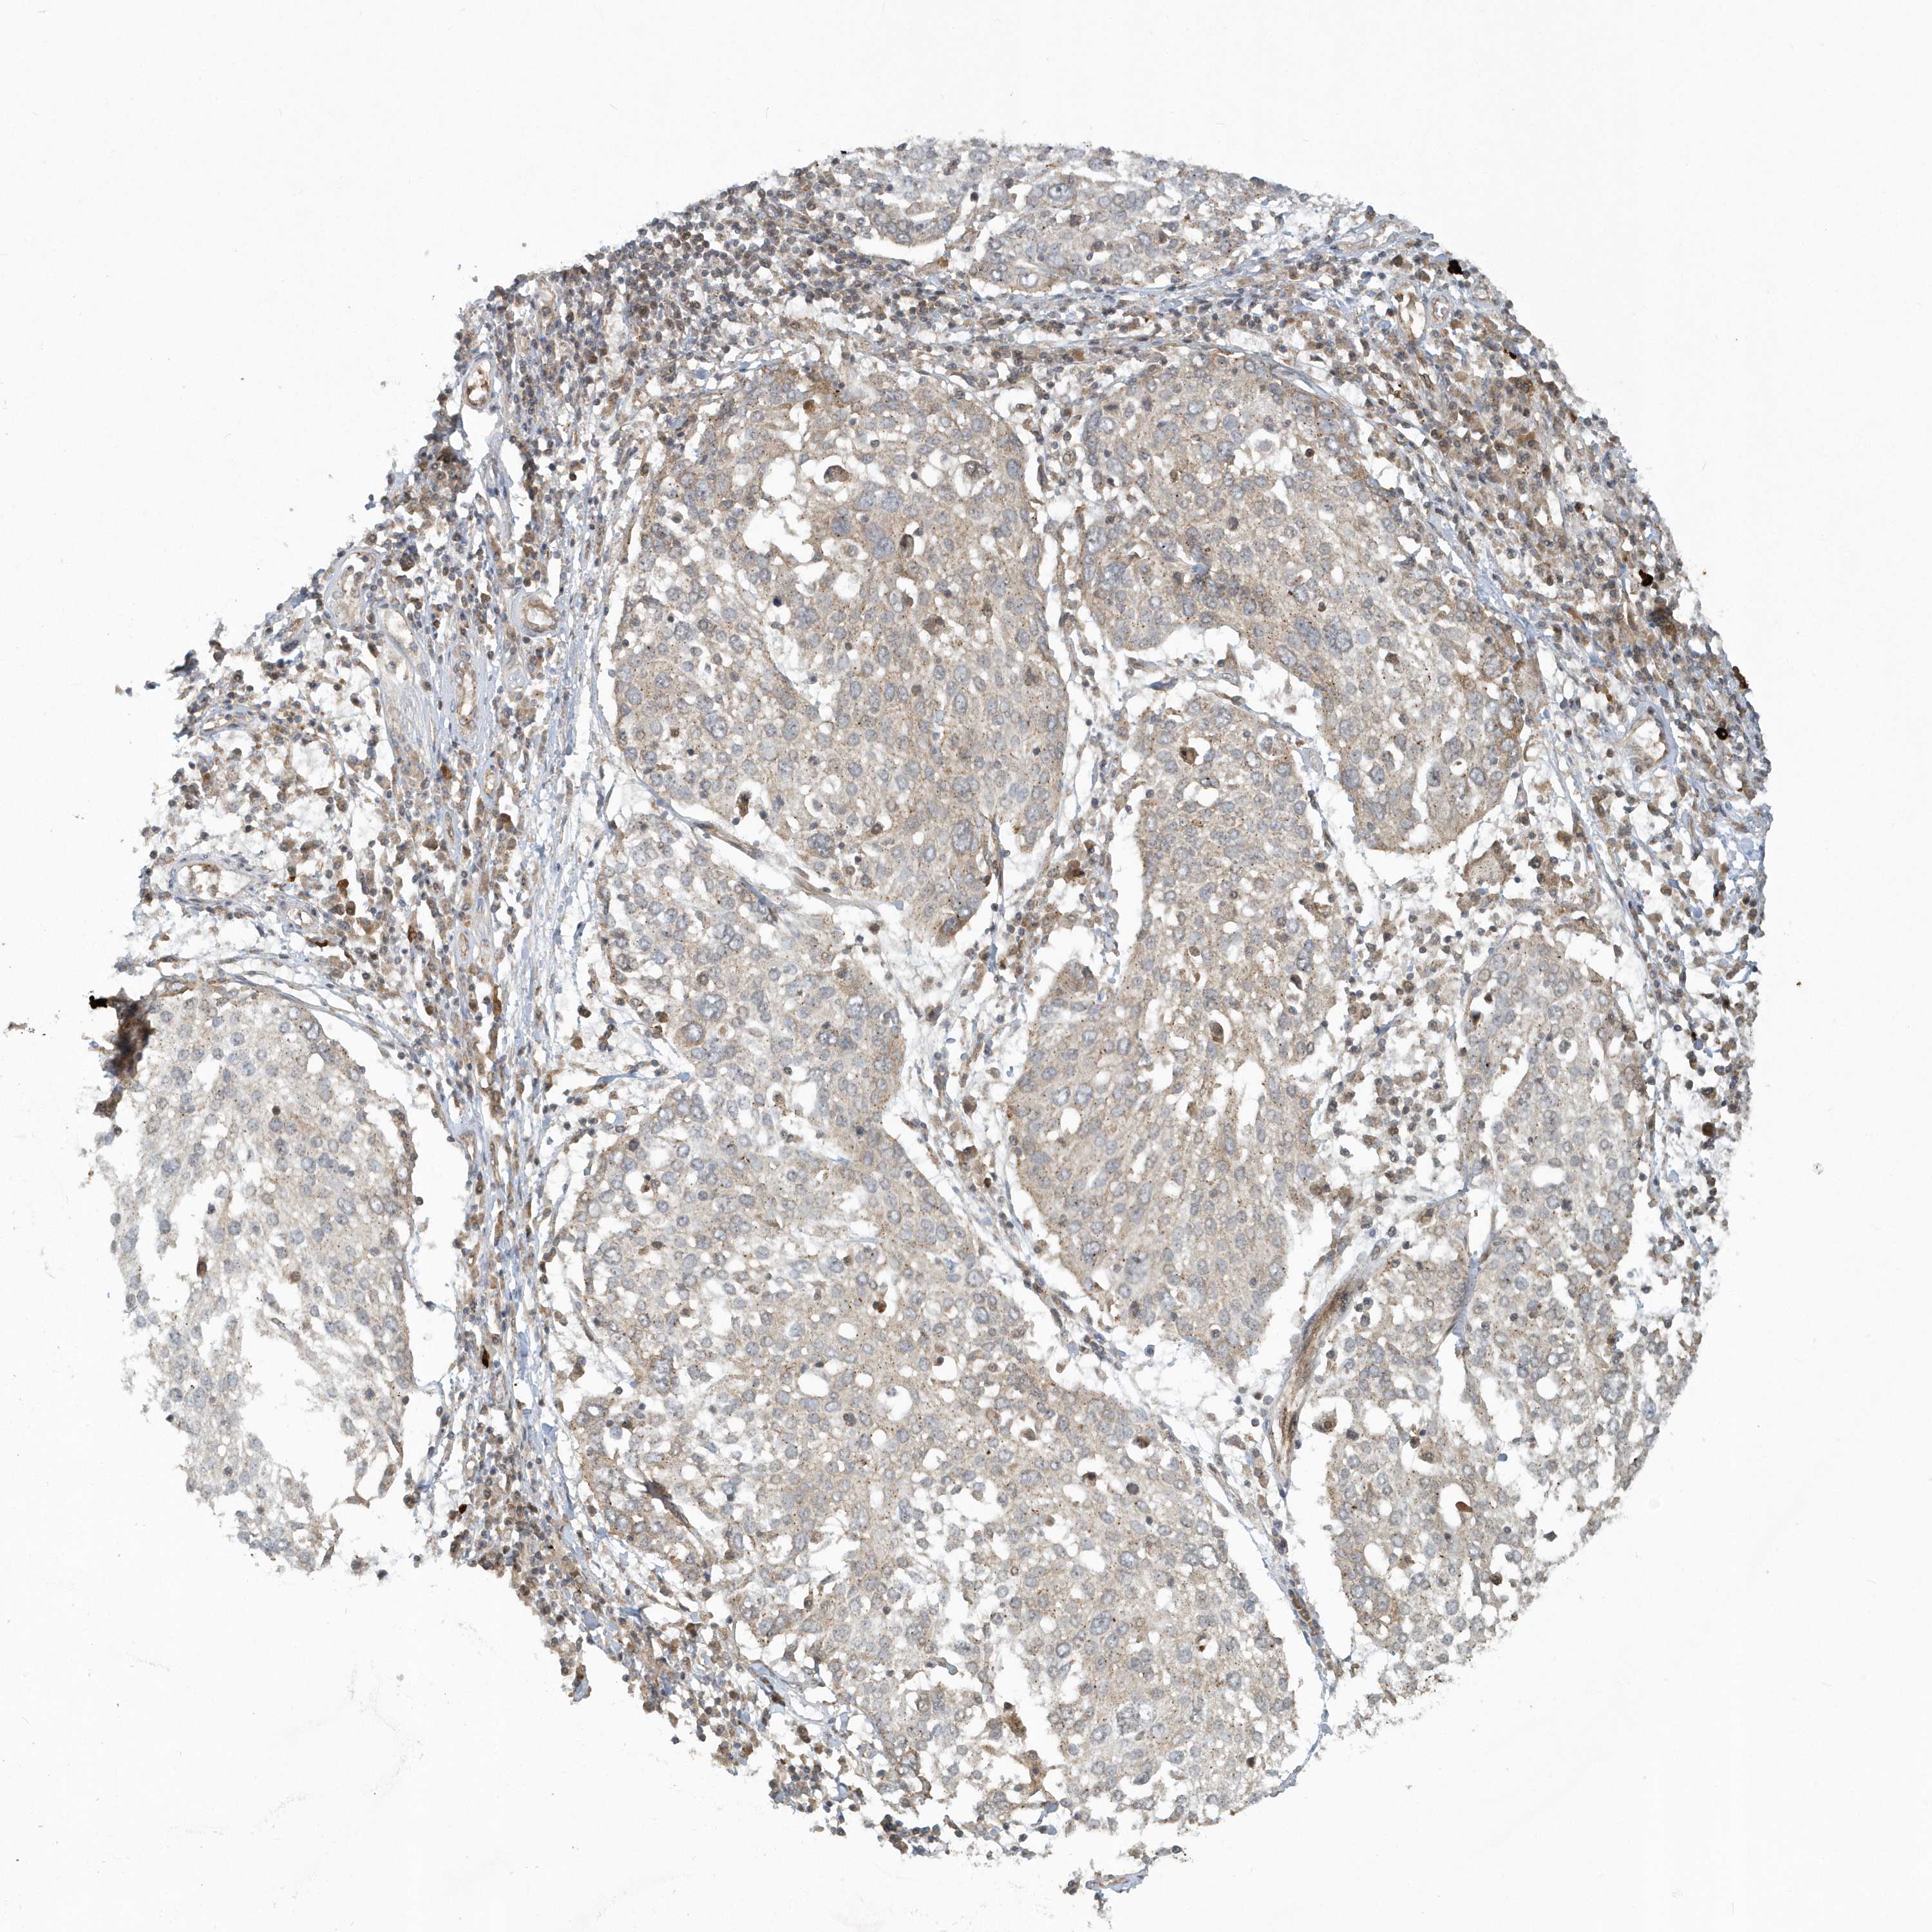

CANCER LUNG CANCER Show tissue menu

LUAD TCGA LUAD VALIDATION LUSC TCGA LUSC VALIDATION PROTEIN LUAD CPTAC PROTEIN LUSC CPTAC PROTEIN EXPRESSION